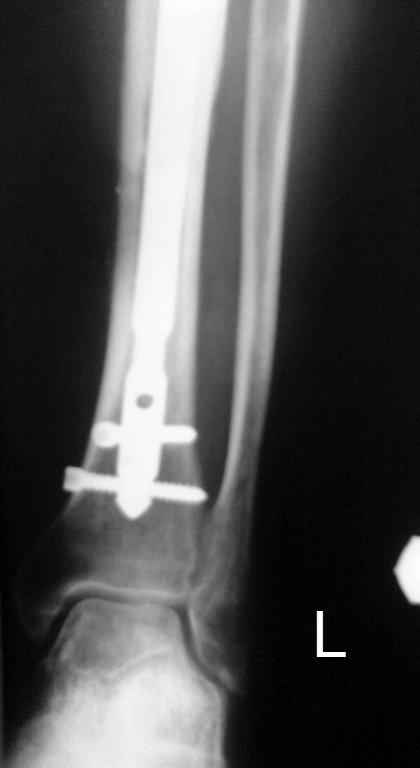

Итак, в настоящий момент больной пришел к нам с полной нагрузкой на оперированную конечность и с такой картиной (см. приложение). Участок мягких тканей с передней стенкой нижней трети ББК, выгнил и представляет дефект 2×2,5 см. На перевязке - циркулярный(?) некроз костной трубки.

Пациенту за 70 лет. Мои соображения: 1 этап - резекция tibia + косая остеотомия fibula + «острое» укорочение + IM цемент-гвоздь с а/б + beads. 2 этап (по заживлению раны) – удаление цемент-гвоздя + (LATN) Lengthening and Then Nailing. Прошу помощи по тактике.Никита Заднепровский

Сегментарного некроза не видно. Есть только краевой дефект спереди, задняя стенка вполне хорошая, и со стержнем есть условия для ее утолщения со временем. Так что проблему должна решить местная санация (если доступно, использовать VAC). Если грануляции не закроют все, что надо закрыть, придется делать пластику полнослойным лоскутом. Идеально бы - с микроососудистым анастомозом.

Позволю высказать свое мнение. У меня есть сомнения, что задняя стенка большеберцовой кости осталась "здоровой". Если после первой операции костная ткань и могла остаться частично жизнеспособной, то развившаяся гнойная инфекция наверняка способствовала окончательному некрозу кости.

Я бы, наверное, после удаления штифта сосредоточился на определения жизнеспособности кости по задней поверхности. Если будут сомнения, то я бы сделал резекцию.

Тогда можно рассмотреть вопрос одновременного удаления штифта, мышечной (в данной области применим проксимально отсеченный лоскут камбаловидной мышцы) или микрохирургической (что более надежно) пластики дефекта мягких тканей, остеотомии проксимального фрагмента большеберцовой кости, остеосинтеза блокируемым штифтом с а/б покрытием, наложения простого аппарата Илизарова (можно из полуколец) для дистракции на штифте. При данном варианте пациент сохраняет возможность полной опоры на ногу, что очень важно для заживления у пожилого пациента) и отпадает необходимость в проведении дополнительный операций (при благоприятном развитии событий).

Выкладываю картинки похожей пациентки. Извините, что без окончательных снимков (сейчас их нет под рукой). Правда мы имели проблемы у данной больной после снятия аппарата, когда промежуточный фрагмент большеберцовой кости сместился на 1,5 см дистально и отошел от проксимальной части кости. До сих пор у пациентки на снимках определяется лишь тонкая полоска кости по задней поверхности за штифтом (образовалось что-то вроде маленького регенерата)в области стыковки промежуточного и проксимального фрагментов. Больная пока решила подождать. Не хочет оперироваться, так как ходит не хромая, работает.